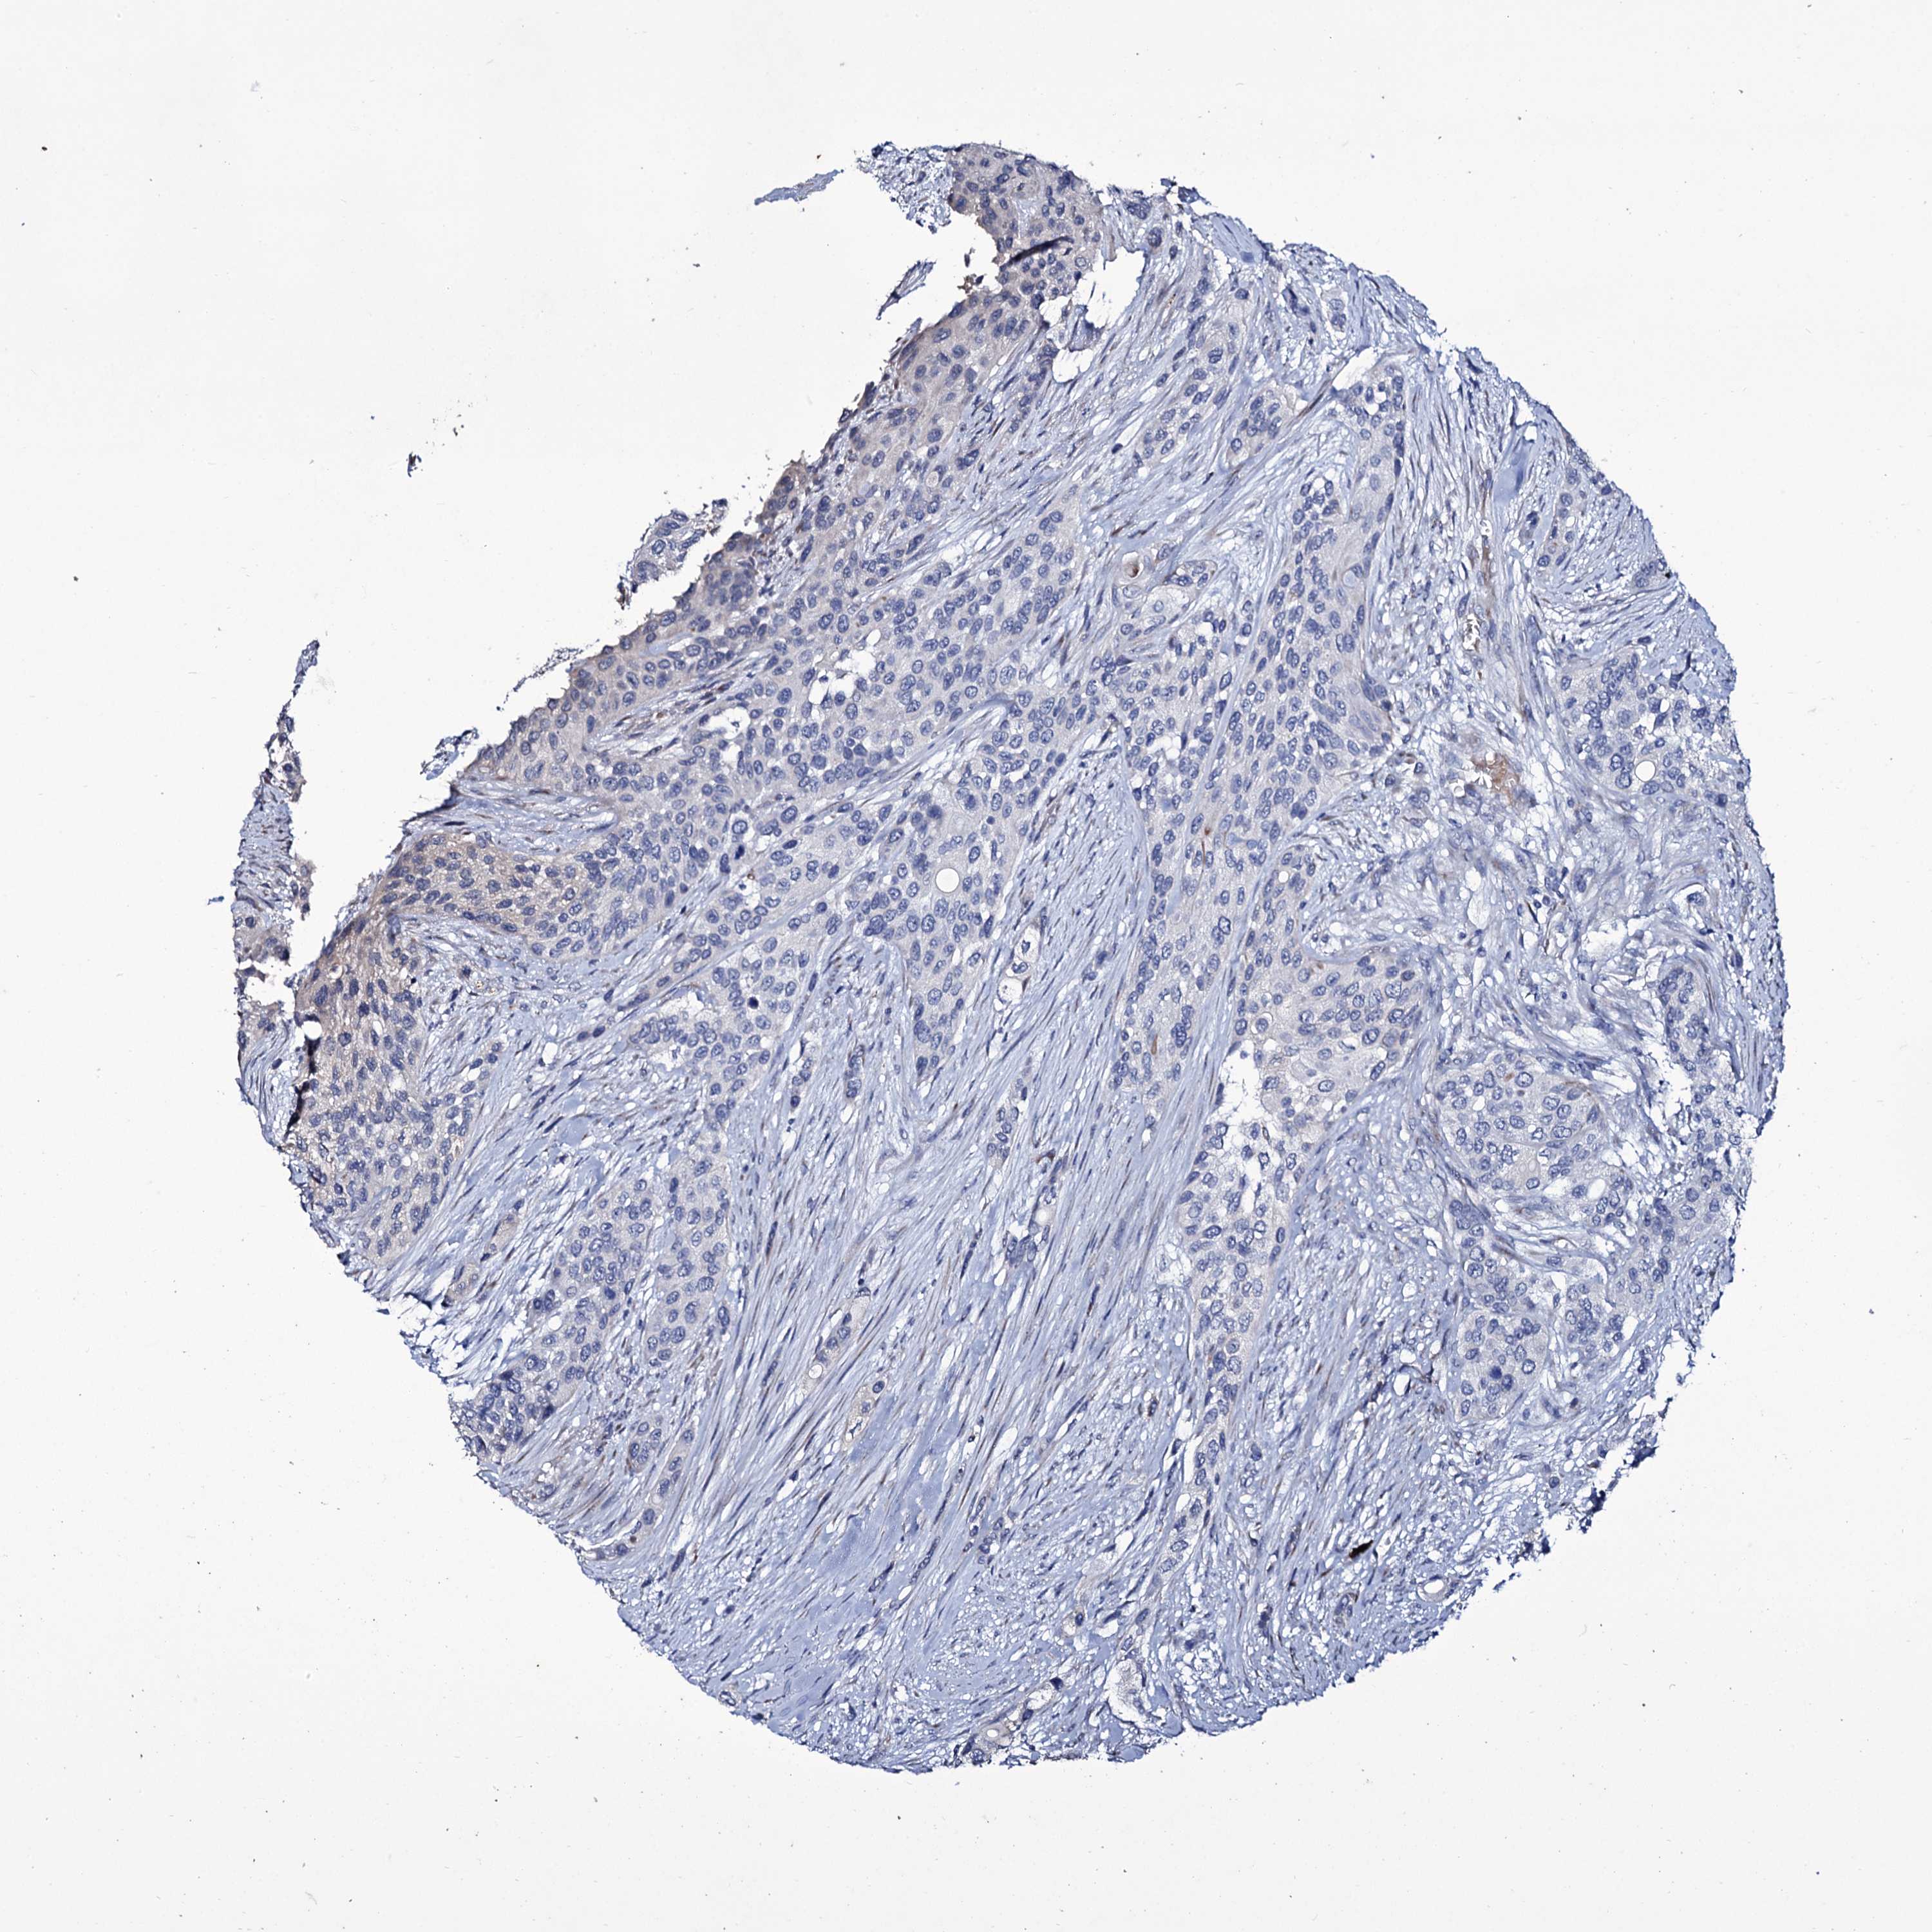

UROTHELIAL CANCER - Protein expressioni

A mouse-over function shows sample information and annotation data. Click on an image to view it in a full screen mode. Samples can be filtered based on level of antibody staining by selecting one or several of the following categories: high, medium, low and not detected. The assay and annotation is described here.

Note that samples used for immunohistochemistry by the Human Protein Atlas do not correspond to samples in the TCGA dataset.

Antibody stainingi

Antibody staining in the annotated cell types in the current human tissue is reported as not detected, low, medium, or high, based on conventional immunohistochemistry profiling in selected tissues. This score is based on the combination of the staining intensity and fraction of stained cells.

Each image is clickable and will lead to virtual microscopy that enables deeper exploration of all samples and also displays staining intensity scores, fraction scores and subcellular localization as well as patient and tissue information for each sample.

Antibody HPA039366

Staining

High

Medium

Low

Not detected

Intensity

Strong

Moderate

Weak

Negative

Quantity

>75%

75%-25%

<25%

None

Location

Urothelial carcinoma, High grade

Urothelial carcinoma, Low grade

Urothelial carcinoma, NOS